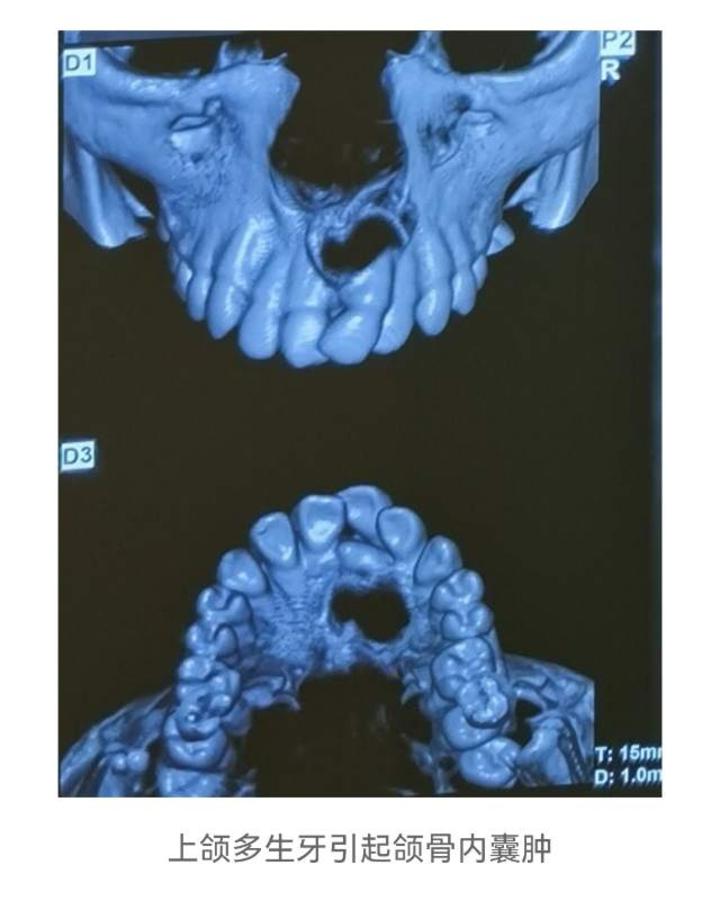

4.颌骨囊肿,含牙囊肿